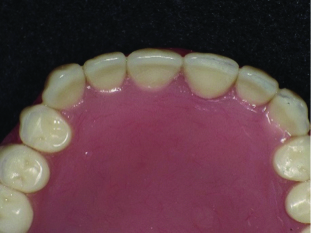

Fig 5. The final denture in the patient’s mouth.

Figure 5

The final delivery required no adjustments on the flanges and the retention was excellent. There were slight adjustments to refine centric occlusion on the bicuspids and to teeth Nos. 9 through 11 to harmonize the excursive function (Figure 4). The final denture can be seen in Figure 5.